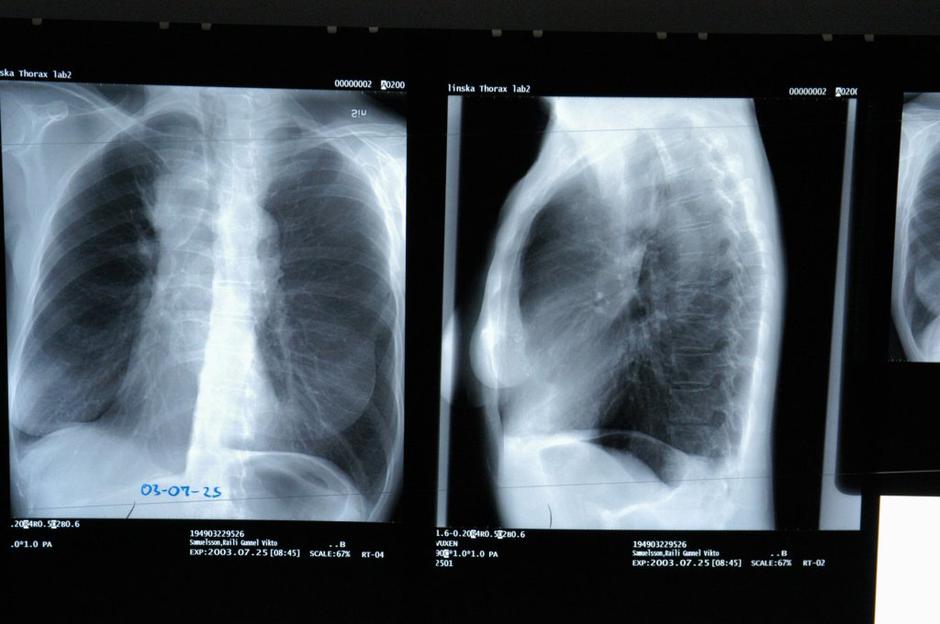

Pljučni rak

V Sloveniji je pljučni rak tretji najpogostejši rak, vsako leto zboli okoli 1600 oseb. Po umrljivosti  je pljučni rak na prvem mestu, saj je vsaka peta smrt, ki jo beležimo zaradi raka, posledica pljučnega raka. Letno tako zaradi pljučnega raka umre okoli 1200 oseb. "Preživetje bolnikov s pljučnim rakom je slabo predvsem zato, ker ga na podlagi simptomov običajno odkrijemo pozno. Če bi ga v presejalnem programu odkrivali prej, bi lahko preprečili veliko smrti. Ker je pljučni rak v veliki meri povezan s kajenjem, je izjemnega pomena, da ob snovanju presejalnega programa v okviru projekta Luka načrtujemo tudi dodatne napore za preprečevanje začetka in opuščanje kajenja," pa pravi Janja Ocvirk, strokovna direktorica Onkološkega inštututa.

Pljučni rak | Avtor: Profimedias Profimedias

"Petletno preživetje bolnikov s pljučnim rakom je okoli 25-odstotno in se le počasi zvišuje. Zdravljenje pljučnega raka je uspešnejše, če ga odkrijemo v zgodnjem stadiju, vendar dovolj zgodaj odkrijemo le okoli 20 odstotkov bolnikov. Pri teh je petletno preživetje več kot 60-odstotno. Kar polovica bolnikov ima ob diagnozi razsejanega raka, ki ga praviloma ne moremo pozdraviti," je dodala

Martina Vrankar, vodja projekta Luka.

Program Luka

Pljučnega raka odkrivajo z uporabo računalniške tomografije (CT) z nizkimi odmerki. V raziskavo bodo vključeni dolgotrajni aktivni ali bivši kadilci, ki nimajo simptomov in so stari od 50-74 let. Cilj presejalnega programa bo po njenem zmanjšati umrljivost za 20–25 odstotkov in povečati delež bolnikov, ki imajo odkrito bolezen v zgodnjem stadiju z 20 na 60 odstotkov.